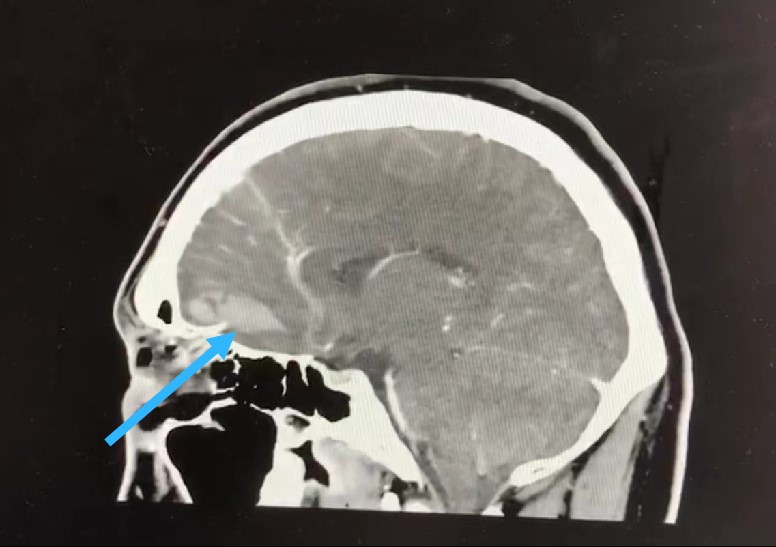

“树枝有没有扎入眼球,扎得有多深?这只眼能不能保住?会不会有更严重的后果?”急诊医生立即联系该院神经外科和耳鼻咽喉科二值医生,启动急诊多学科联合诊治,同时进行了手术前准备。眼眶、头颅CT平扫+三维重建+CTA检查显示,异物自右眶下皮肤进入,经右眼球内侧旁进入筛窦,并突破颅底硬脑膜进入右侧额叶。

中山一院神经外科郭少雷副教授、杨毅兵医生,眼科万鹏霞主任、苏毅华医生以及鼻喉科李健主任共同研究病情。郭少雷副教授介绍,此次手术存在三大难点。首先,患者伤情严重,表面上看是树枝插入眼部,但经过CT检查,异物的末端已插入颅底,且脑部出现了血肿,手术风险极大。其次,这种植物性异物带有较多细菌、真菌等微生物,手术过程中对于伤口的清创要做到万分仔细,保证异物无残留,预防颅内感染的发生。最后,取出异物后必须修补已发生骨折的颅骨,降低颅内感染的风险,否则后果不堪设想。

尽管伤情严重,但不幸中的万幸在于,病情影像检查提示,异物没有损伤眼球及颅底重要血管,通过联合手术,成功取出异物的机会很高。